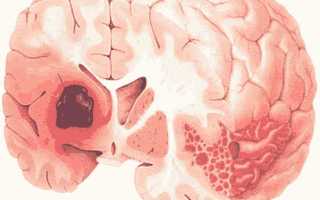

- Инсульт. Инсульты, в свою очередь, делятся на два типа: геморрагические, при которых происходит кровоизлияние в мозговые ткани из-за разрыва сосуда, и ишемические, когда кровеносный сосуд блокируется по различным причинам, что приводит к недостатку кислорода в мозге.

Геморрагический инсульт возникает, когда кровь из поврежденного сосуда проникает в мозг. Это может привести к сдавлению мозговой ткани, что вызывает различные повреждения, иногда заканчивающиеся летальным исходом.